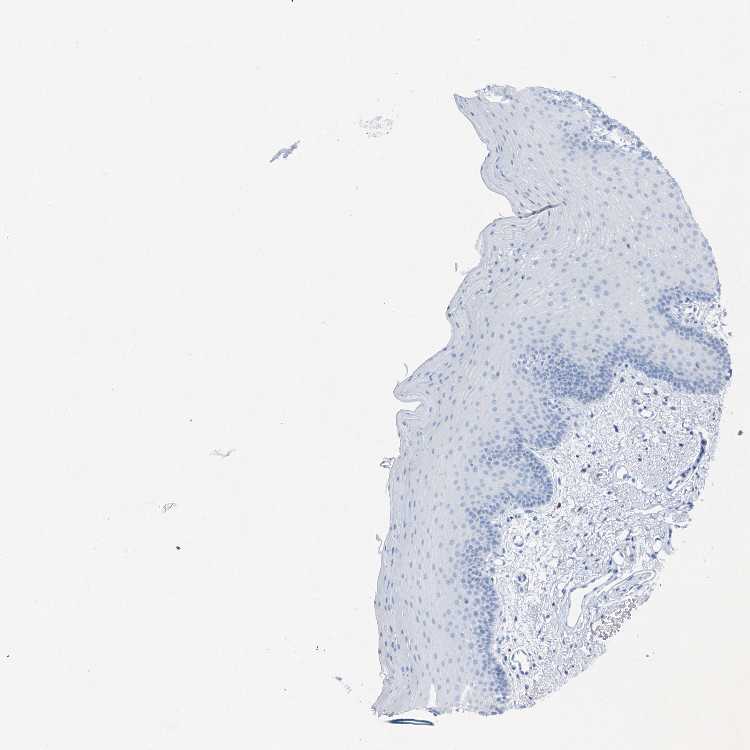

TISSUE PRIMARY DATA ORAL MUCOSA Show tissue menu

ORAL MUCOSA - Antibody stainingi

Antibody staining in the annotated cell types in the current human tissue is reported as not detected, low, medium, or high, based on conventional immunohistochemistry profiling in selected tissues. This score is based on the combination of the staining intensity and fraction of stained cells.

Each image is clickable and will lead to virtual microscopy that enables deeper exploration of all samples and also displays staining intensity scores, fraction scores and subcellular localization as well as patient and tissue information for each sample.

Antibody HPA041032

Squamous epithelial cells Not detected